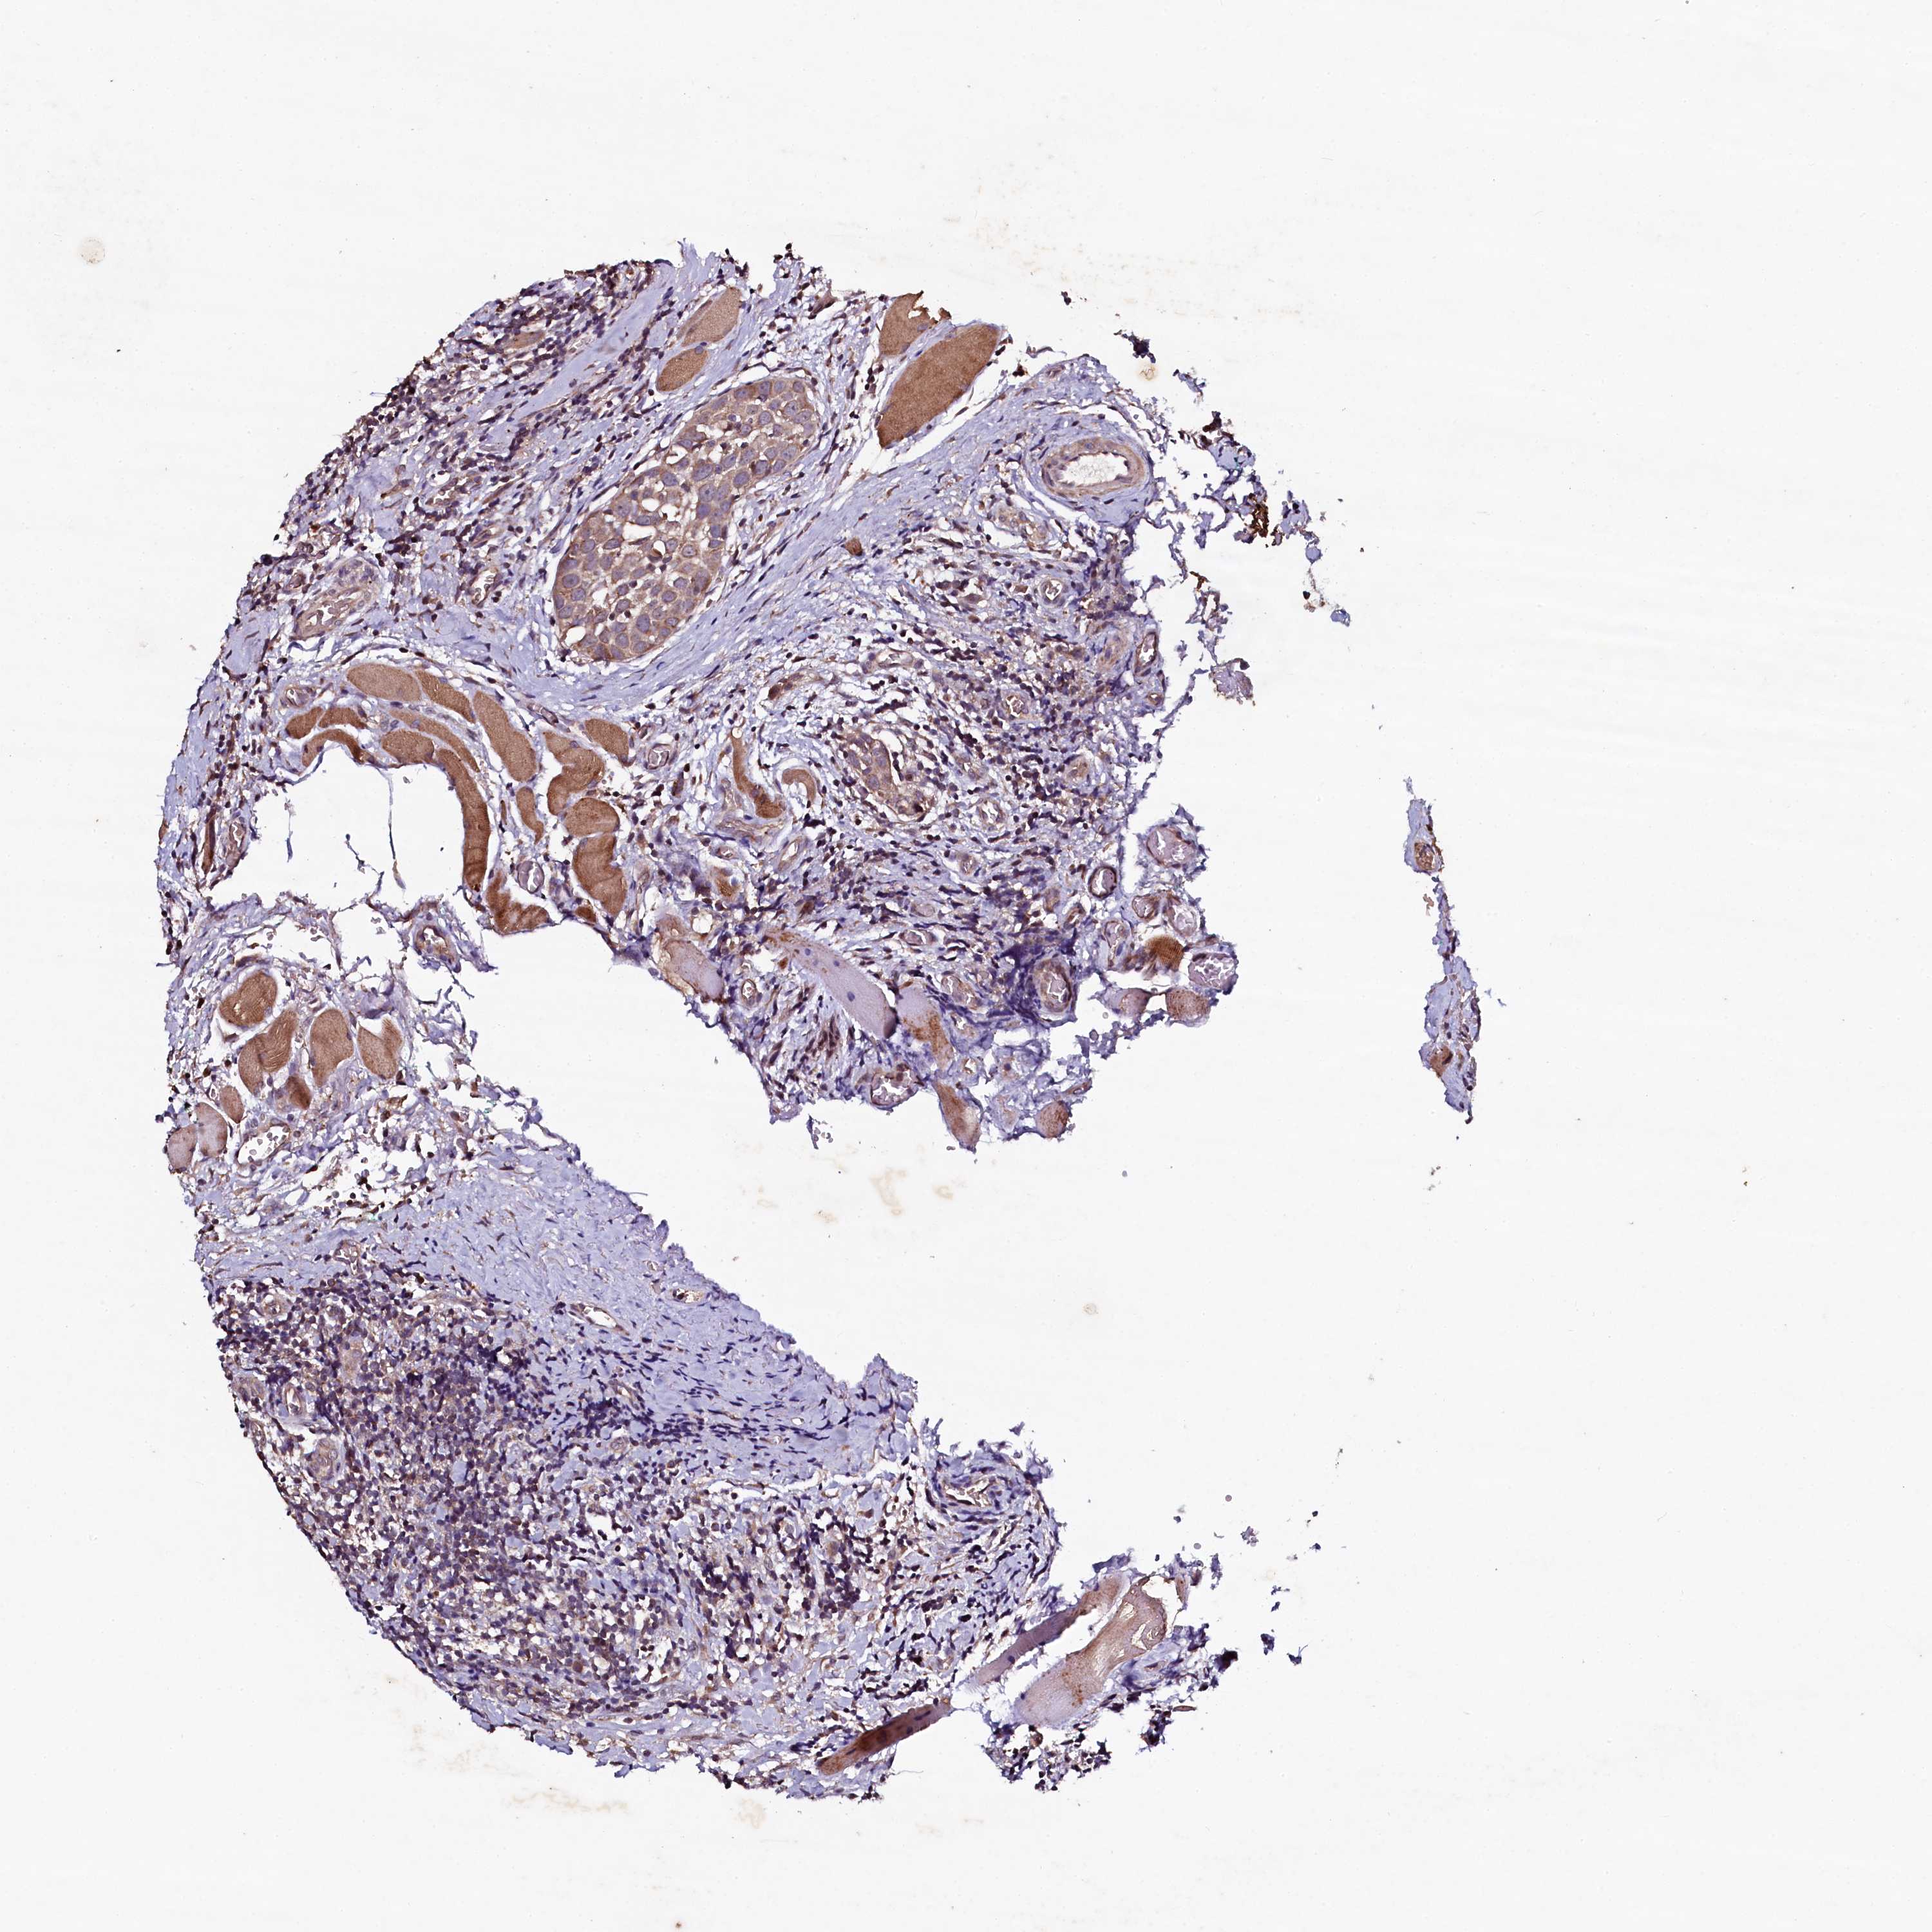

HEAD AND NECK CANCER - Protein expressioni

A mouse-over function shows sample information and annotation data. Click on an image to view it in a full screen mode. Samples can be filtered based on level of antibody staining by selecting one or several of the following categories: high, medium, low and not detected. The assay and annotation is described here.

Antibody stainingi

Antibody staining in the annotated cell types in the current human tissue is reported as not detected, low, medium, or high, based on conventional immunohistochemistry profiling in selected tissues. This score is based on the combination of the staining intensity and fraction of stained cells.

Each image is clickable and will lead to virtual microscopy that enables deeper exploration of all samples and also displays staining intensity scores, fraction scores and subcellular localization as well as patient and tissue information for each sample.

Antibody HPA040196

Antibody HPA040213

Staining

High

Medium

Low

Not detected

Intensity

Strong

Moderate

Weak

Negative

Quantity

>75%

75%-25%

<25%

None

Location

Nuclear

Cytoplasmic/membranous

Cytoplasmic/membranous,nuclear

Squamous cell carcinoma, NOS

Adenocarcinoma, NOS